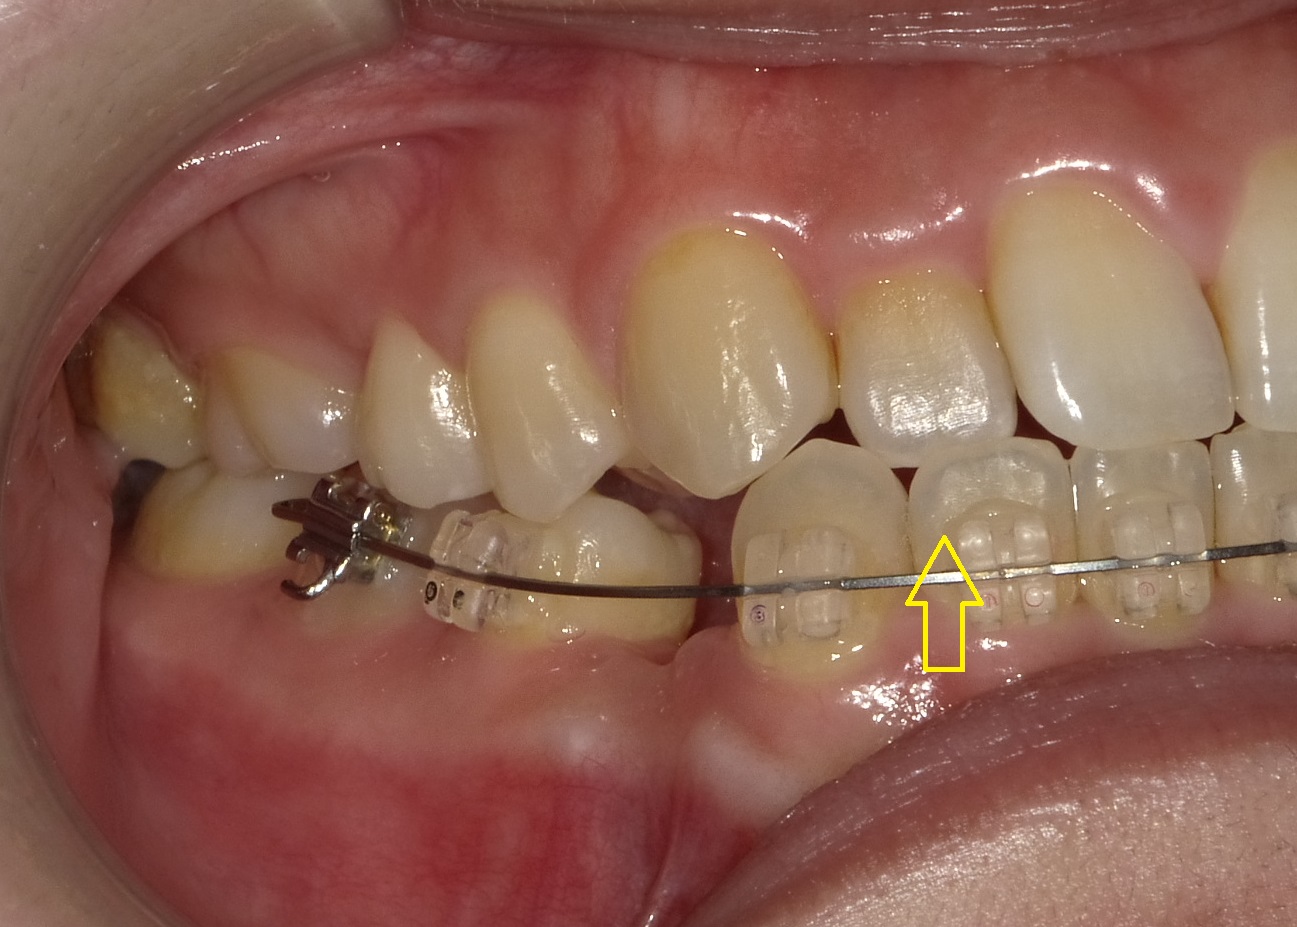

写真は抜歯後2週間ほど空けて、歯茎の治りをみて、2週間ほど下の前歯を奥へと引っ張っている状態です。

矢印の交差している部分は勿論まだまだ改善はしておらず、その引っ掛かりを無視して下の前歯を後ろに引いているため、下の前歯に多少の隙間が出来ています。

あまりに引っかかっている量が多い場合は「患者さんの不快感」や「歯の摩耗」等につながるため、回避処置が必要になりますが、この程度のものであれば無視しても構わないことが多いため、無理のない程度に力を掛けて下の前歯を引っ込めていきます。

次回は前歯の交差を確認、必要であれば噛み合わせを一時的に挙げていきます。